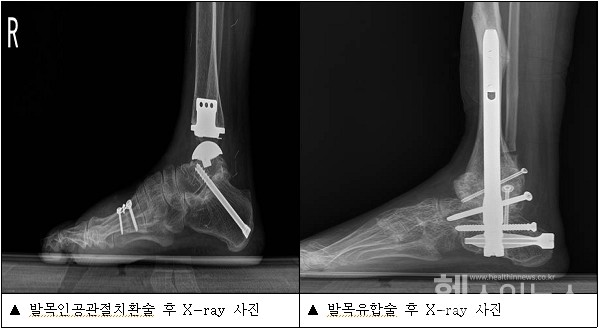

발목 인공관절치환술은 수술 후 발목의 가동 범위가 제한적인 발목유합술에 비해 정상적인 가동이 가능하고, 이로 인해 주변 관절의 퇴행성 관절염도 예방할 수 있다는 장점이 있다. 그러나 무릎이나 고관절의 인공관절치환술에 비해 수술의 난이도가 높고, 수술장비의 기술적 발전이 부족해, 5년 이내 다시 수술을 받거나 발목유합술로 교체하는 비율이 높다. 따라서 환자의 상태에 따라 적합한 수술 방법을 선택하는 것이 중요한데, 이때 기저질환 유무가 조기실패에 영향을 끼치는 것으로 나타났다.

연구팀은 2007년부터 2016년까지 한국건강보험공단에 등록된 발목 인공관절치환술을 받은 2157명을 분석했다. 이중 수술 후 5년 이내 인공관절을 제거하거나 재치환술을 받은 환자, 발목유합술을 받은 환자는 조기실패 그룹으로 분류했다. 조기실패 그룹은 197명이었으며 이는 전체의 9.1%를 차지했다.